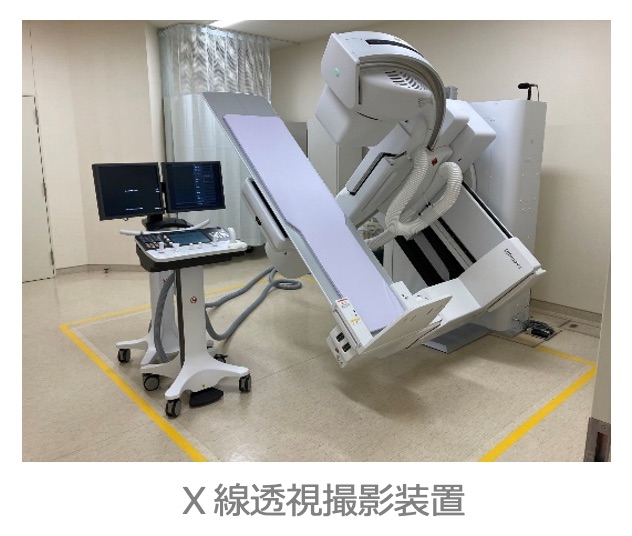

| 透視検査治療 | 3室 | X線透視撮影装置(フラットパネルディテクタ搭載)×3台 |

| 救命救急 | 5室 | 一般撮影装置(フラットパネルディテクタ搭載)×1台 X線透視撮影装置(フラットパネルディテクタ搭載)×1台 80列MDCT×1台 3.0T MRI×1台 脳血管撮影用装置(フラットパネルディテクタ搭載)×1台 |

X 線透視検査治療

●透視検査のよくある質問